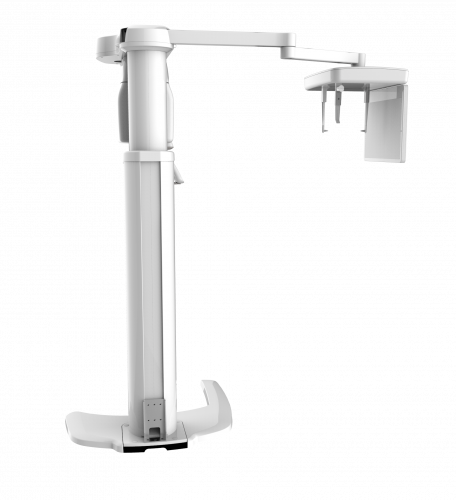

| TYPE | TOP VIEW | FRONT VIEW |

|---|---|---|

|

PaX-i (Pano) |

|

|

|

PaX-i SC (Pano/Scan Ceph) |

|

|